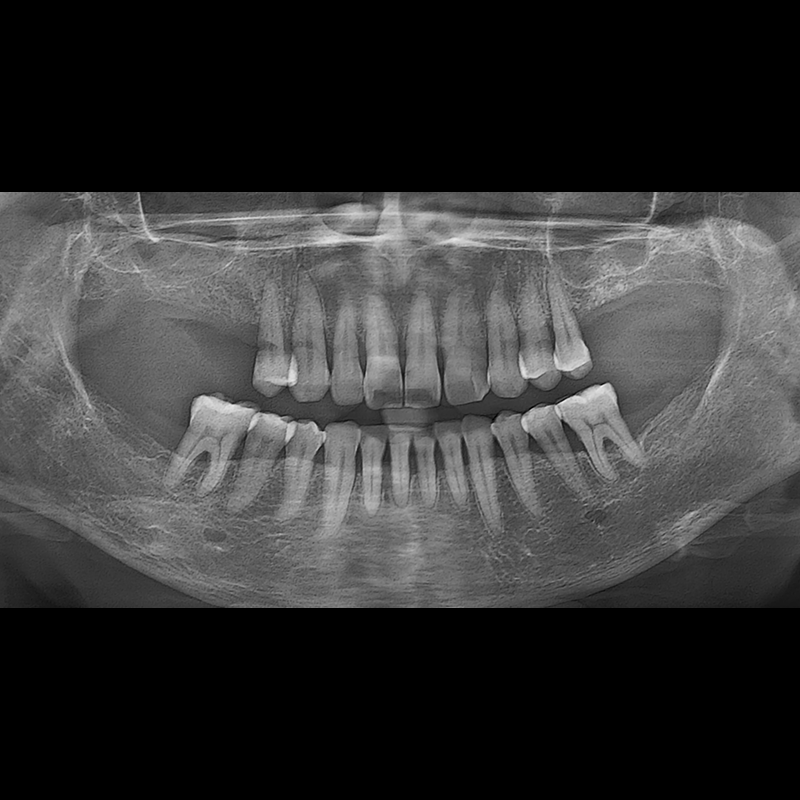

BEFORE AFTER

임플란트 전후사진 2025.05.30

결손된 치아 부분과 살리기 힘든 치아 위치에 임플란트를 식립하였습니다.